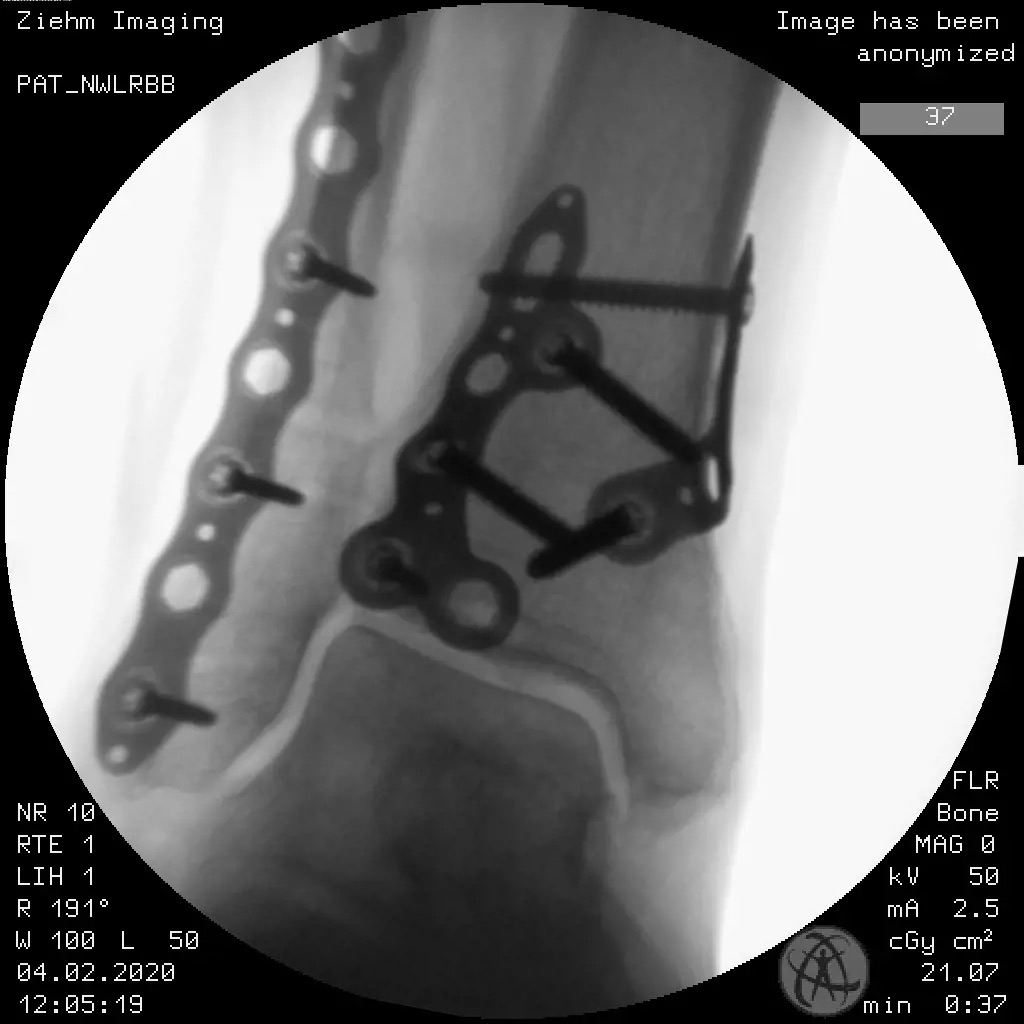

Volition® Ankle Fracture Plating

• VolitionTM Ankle Fracture Plates are available in six varieties: anatomic fibula plate, straight fibula plate, anatomic medial malleolar plate, posteromedial tibial plates (Type IIB), posterolateral tibial plates (Type IIA) and posterior tibial plates (Type III).

• confirm positioning in 2 planes with fluoroscopy